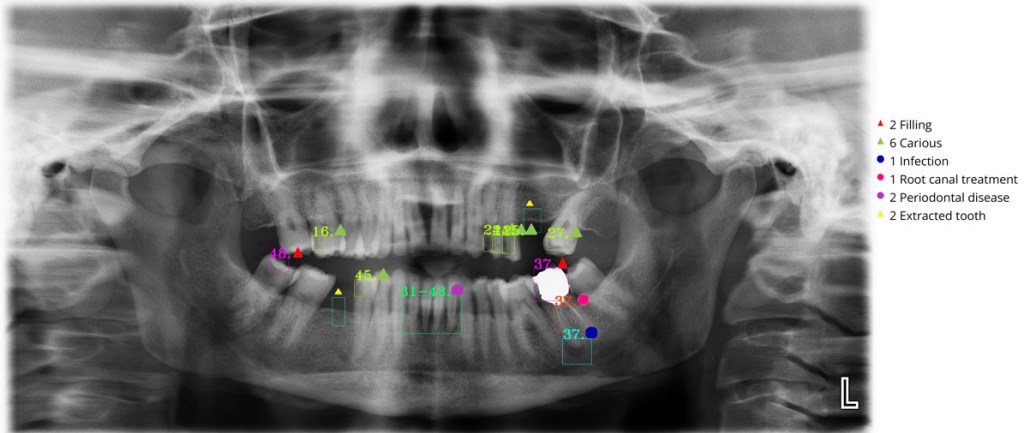

This study aimed to identify tooth numbering and dental treatments in X-ray images, such as implants, infections, caries, fillings, root canal treatments, extracted teeth, impacted teeth, bridges, and crowns (Fig. 2 and 3).

Figure 3. Dental AI application results.